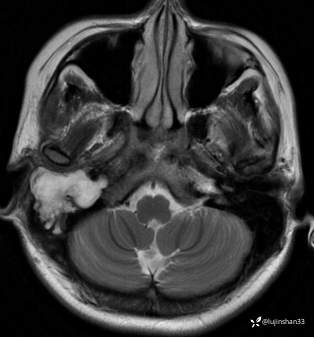

颞骨MRI: